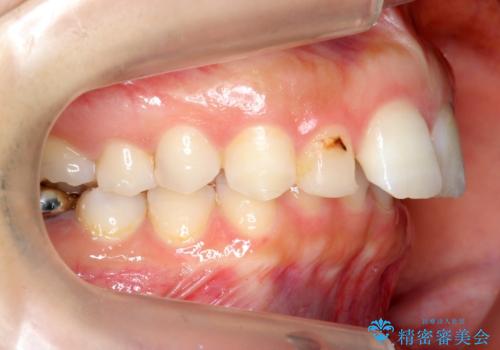

- 出っ歯を主訴に来院。

かみ合わせが深く、治療に時間がかかりました。

上顎2番は矮小歯だったのをセラミックで被せています。

口唇の突出感がなくなり、理想的な横顔になりました。